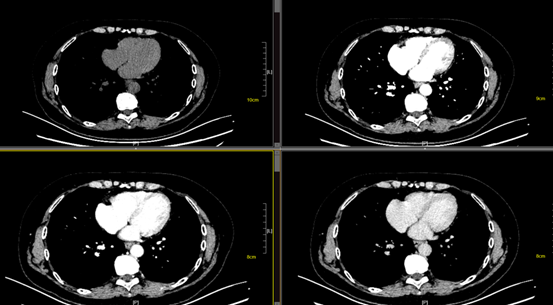

CT增强

CT增强使用的是碘对比剂,碘对比剂通过吸收X线,直接衰减X线,从而减少能穿透人体并到达胶片的X线量,这使局部组织(如血管和病变)在CT图像中形成高密度或较亮区域。CT检查价格相对便宜,检查时间较短,对骨质、钙化更加敏感,尤其对肺部病灶的显示有其独特的地位,但CT检查有一定的辐射。